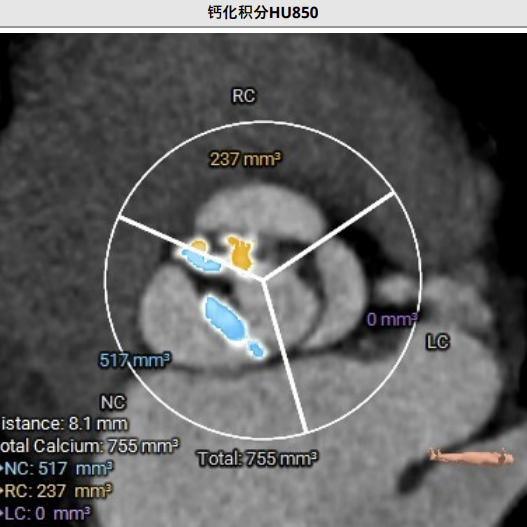

术前CT评估:

CT分析提示:TypeI型二叶瓣,左右瓣叶融合,瓣叶增厚,重度偏心性钙化,钙化位于无冠瓣叶及右无瓣叶交界处,且钙化延伸至LVOT2.5mm,舒张期可见瓣叶关闭不全间隙,右冠高度可,左冠开口平面可见瓣叶,左冠堵塞风险极高,心室略大,室壁厚度可,非横位心,升主动脉瘤样扩张,大血管走行自然,右侧髂总动脉血管细小。